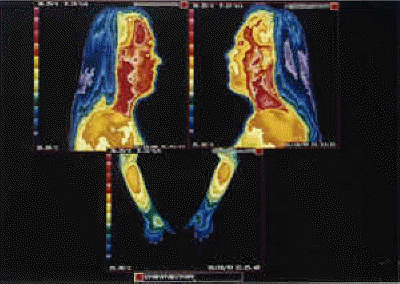

Virtual Sympathectomy Thermography.

"Virtual sympathectomy" secondary to repeated stellate ganglion nerve blocks leading to permanent sympathetic nerve damage and hyperthermia (heat leakage) in upper extremities. The ITI spared the patient from further sympathetic nerve blocks.